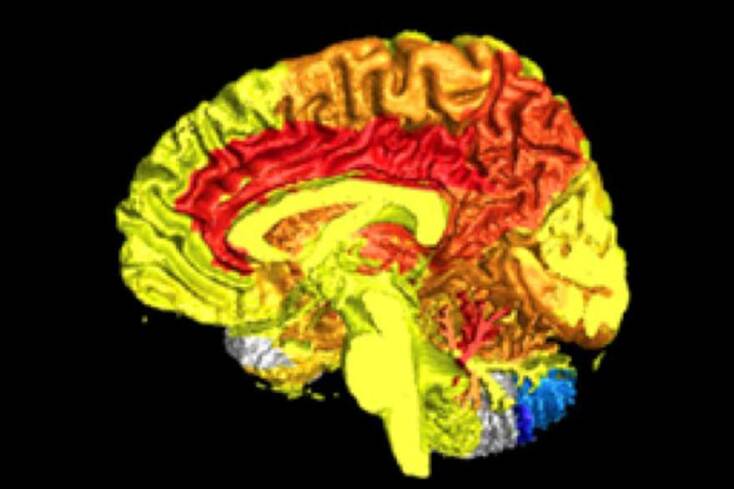

Σε περίπτωση, λοιπόν, που αναρωτιόσασταν, μία έρευνα του Πανεπιστημίου του Τέξας απέδειξε ότι είχατε δίκιο κάθε φορά που βάζατε στοίχημα ότι αποκλείεται ο εγκέφαλος του ατόμου του αντίθετου φύλου που έχετε μπροστά σας, να λειτουργεί με τον ίδιο τρόπο με τον δικό σας. Οι ερευνητές οδηγήθηκαν στο τελικό τους πόρισμα μετά τη μελέτη και τη σύγκριση 46.000 εγκεφαλογραφημάτων εθελοντών από εννιά διαφορετικές κλινικές, όπου παρατήρησαν σε ποιες περιοχές του εγκεφάλου η ροή του αίματος αυξανόταν κατά τη διάρκεια διαφορετικών δραστηριοτήτων αλλά και της ξεκούρασης.

Με αυτόν τον τρόπο εντόπισαν τις 128 διαφορετικές εγκεφαλικές περιοχές που φαίνονται στην εικόνα. Από αυτές, οι κόκκινες είναι εκείνες στις οποίες οι γυναίκες εμφάνισαν αύξηση της ροής του αίματος και οι μπλε, αντίστοιχα, αυτές που η ροή αυξήθηκε στους άντρες.

Οι κόκκινες περιοχές σχετίζονται με τη συγκέντρωση, τις παρορμήσεις μας και τα συναισθήματα. Αυτό σημαίνει ότι οι γυναίκες παρουσιάζουν μεγαλύτερη ενσυναίσθηση, διαίσθηση και αυτοέλεγχο, ενώ έχουν μία τάση να δουλεύουν καλύτερα ομαδικά και είναι ικανές να φροντίζουν τους άλλους. Την ίδια, όμως, στιγμή είναι επιρρεπείς στην κατάθλιψη, σε αγχώδεις διαταραχές και στη νόσο του Αλτσχάιμερ.

Από την άλλη, η αύξηση της ροής του αίματος στις μπλε περιοχές υποδεικνύει ότι οι άντρες έχουν καλύτερο συντονισμό, οπτική κατανόηση και τα πηγαίνουν καλύτερα στις σωματικές δραστηριότητες. Παράλληλα, έχουν αρκετά λιγότερες πιθανότητες να νοσήσουν με Αλτσχάιμερ, αλλά είναι αρκετά πιθανό να πάσχουν από ADHD, δηλαδή διάσπαση προσοχής, ενώ οι ερευνητές επισημαίνουν ότι οι άντρες είναι κατά 1.400% πιθανότερο να καταλήξουν στη φυλακή.